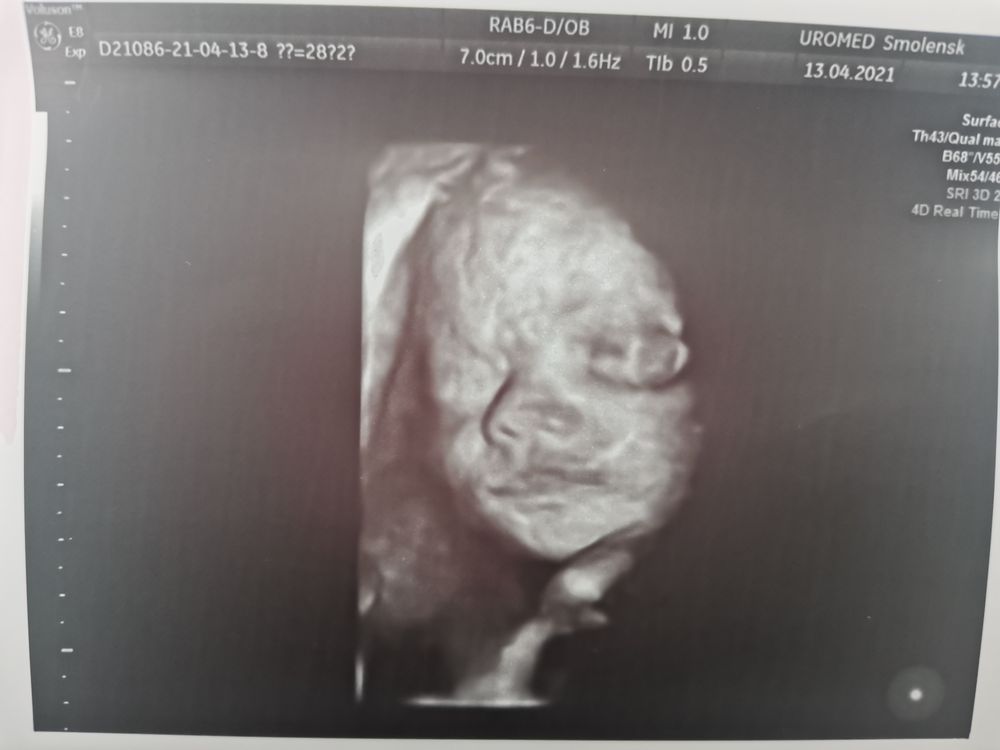

Ещё я сходила на УЗИ в 28 недель посмотреть на нашу лялю и у нас все ОТЛИЧНО ☺️✨

Сегодня в 29.5 недель была на УЗИ в роддоме (врач направил) и тоже все хорошо ☺️ Ева сосала пальчик и пинала узиста 😄

Предлежание у нас головное, правда пуповинкой обмоталась, но это не страшно 😌